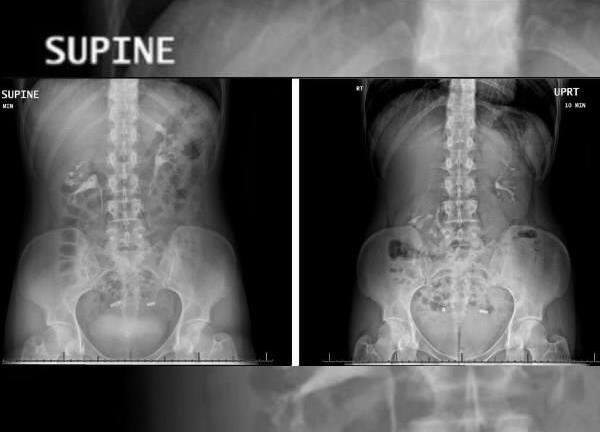

Trường hợp hy hữu này xảy ra ở Mỹ, một người phụ nữ 28 tuổi sống tại bang Michigan mắc chứng quả thận “nổi”, tức là, quả thận sẽ rơi xuống xương chậu mỗi khi cô ấy đứng lên.